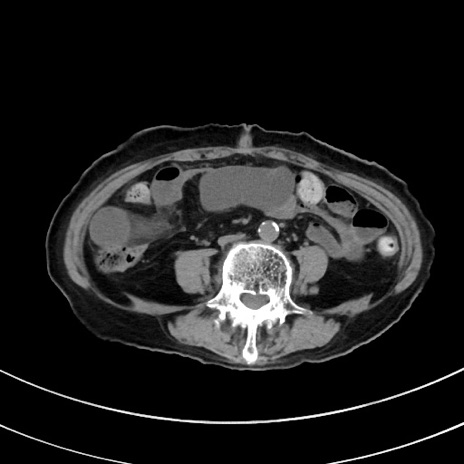

症例33(横断像)

【症例】70歳代 女性

【主訴】心窩部痛

【現病歴】延髄病変の精査・加療にて神経内科入院中。本日より心窩部痛あり。

【身体所見】右下腹部を中心に圧痛と反跳痛あり。

【データ】WBC 10900、CRP 0.02